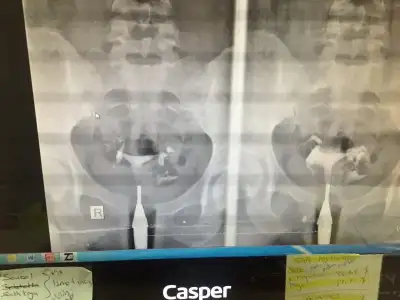

kendılıgındenmı hamıle kaldın cnm. yoksa aşılama falanmıBen o riski alamadım. Hamile kalmak eninde sonunda olur hiçbir sıkıntınız yokmuş. Ama o gebeliğin devamı için garanti veriyor mu doktorunuz? Ben ilk teşhis konulduğunda Bezmialem vakıf üniversitesi hastanesine gidiyordum. Sonra bazı sebeplerden orda operasyon olamadım ama orda da çok fazla ödeme yapılmıyor herşey ücretsiz zaten muayeneler testler. Heyete bile girmiştim ama sabırsızlıktan gittim başka doktorda oldum. Histeroskopi size sadece 2 ay kaybettirir. Sonra zaten korunmanıza gerek Yok yada aşılama olacaksa olur. Ben son operasyondan 8 ay sonra hamile kaldım. Karar size ait. Risk alacağım diyorsanız en fazla bir ayınız ve bir miktar paranız gider.